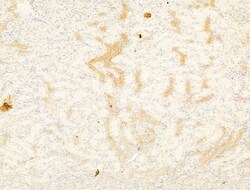

| Immunocytochemistry, Immunohistochemistry (Paraffin), Western Blot | |